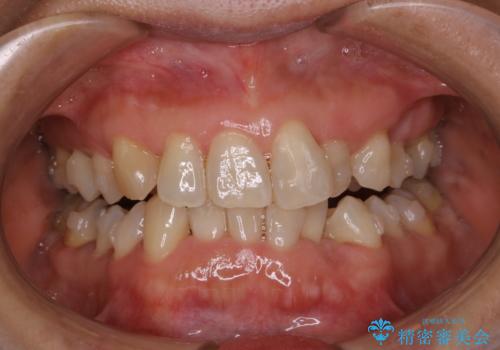

インビザラインの治療中の患者様のクリーニング前後写真です。

- インビザラインの矯正治療中に歯石や着色(ステイン)が付着してしまっていたため、歯科衛生士による専門的クリーニングを行いました。

今回はお口全体に歯石や着色(ステイン)が付着していたため、自費のPMTC(クリーニング)60分コースをご案内し、徹底的に除去しました。